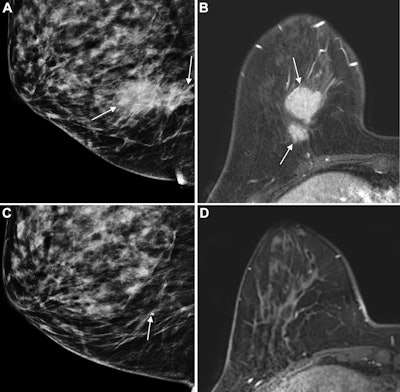

Images of the right breast in a 63-year-old woman with estrogen receptor–low, HER2–positive breast cancer. (A) Mediolateral oblique mammogram obtained before neoadjuvant chemotherapy shows a 5-cm, irregular, spiculated, hyperdense mass (arrows) without calcification in the lower central breast. (B) Axial contrast-enhanced T1-weighted MRI scan obtained before chemotherapy shows two abutting malignant masses (arrows) in the lower central breast. (C) Mediolateral oblique mammogram after chemotherapy shows a decrease in tumor size, with only a biopsy marker (arrow) at the corresponding site. (D) Axial contrast-enhanced T1-weighted MRI scan after chemotherapy shows no residual enhancement in the tumor bed. This radiologic complete response corresponded with pathologic complete response, as determined via pathologic examination after breast-conserving surgery.Images of the right breast in a 63-year-old woman with estrogen receptor–low, HER2–positive breast cancer. (A) Mediolateral oblique mammogram obtained before neoadjuvant chemotherapy shows a 5-cm, irregular, spiculated, hyperdense mass (arrows) without calcification in the lower central breast. (B) Axial contrast-enhanced T1-weighted MRI scan obtained before chemotherapy shows two abutting malignant masses (arrows) in the lower central breast. (C) Mediolateral oblique mammogram after chemotherapy shows a decrease in tumor size, with only a biopsy marker (arrow) at the corresponding site. (D) Axial contrast-enhanced T1-weighted MRI scan after chemotherapy shows no residual enhancement in the tumor bed. This radiologic complete response corresponded with pathologic complete response, as determined via pathologic examination after breast-conserving surgery.RSNA